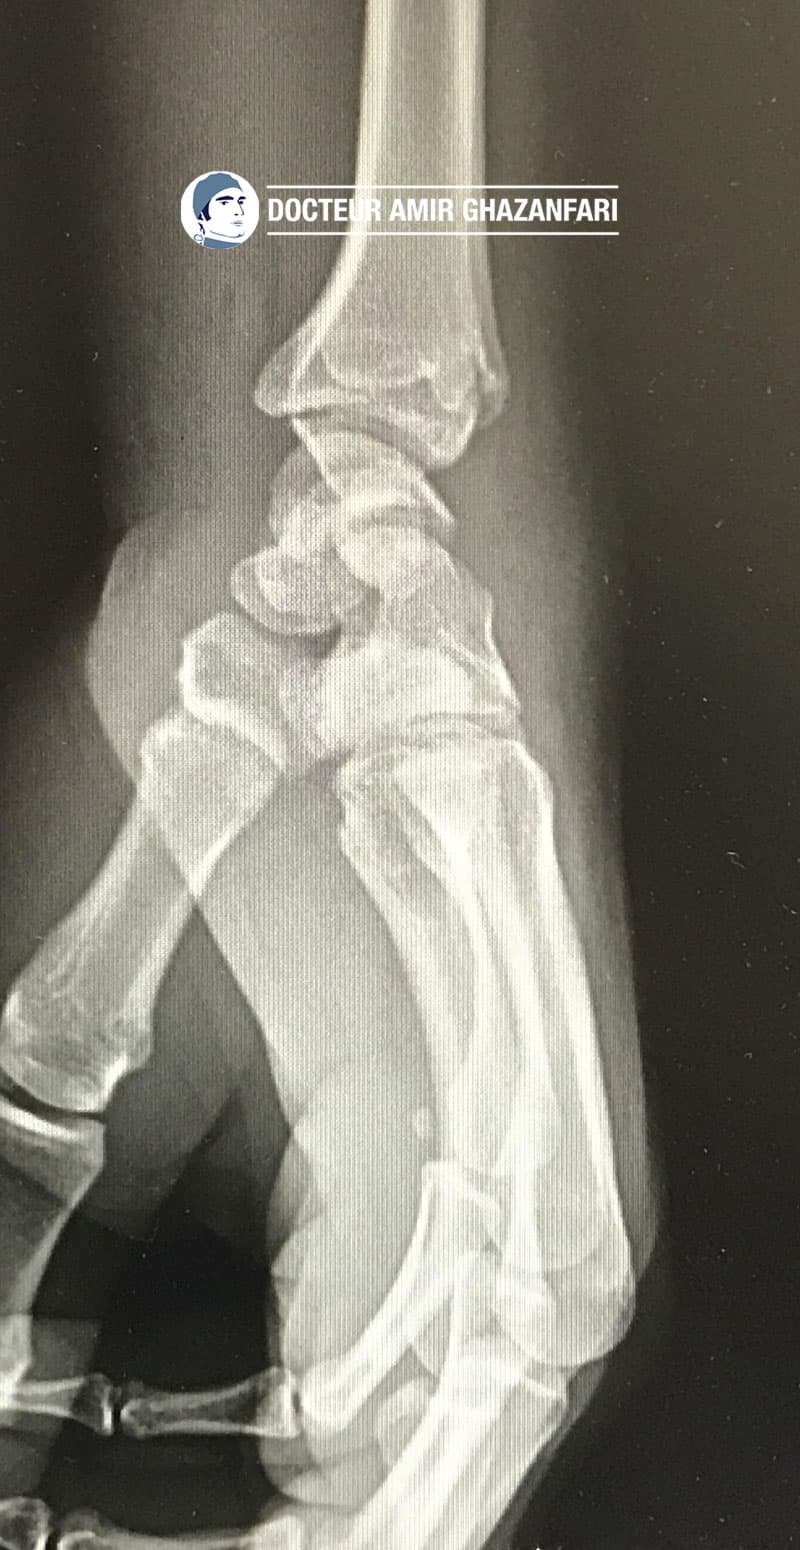

Fracture du scaphoïde Diagnostic et traitement from docteurghazanfari.com

Fracture du scaphoïde Diagnostic et traitement

Fracture du scaphoïde Diagnostic et traitement. Dans le traitement d'une fracture du scaphoïde, les mesures immédiates recommandées sont l'élévation du bras, le refroidissement avec des compresses réfrigérantes et le repos du bras.Une imagerie médicale est généralement utilisé pour voir comment et où exactement le scaphoïde est cassé. Peut-on travailler avec une fracture du scaphoïde ? Ceci va dépendre du type de fracture, ainsi que des exigences physiques du travail..